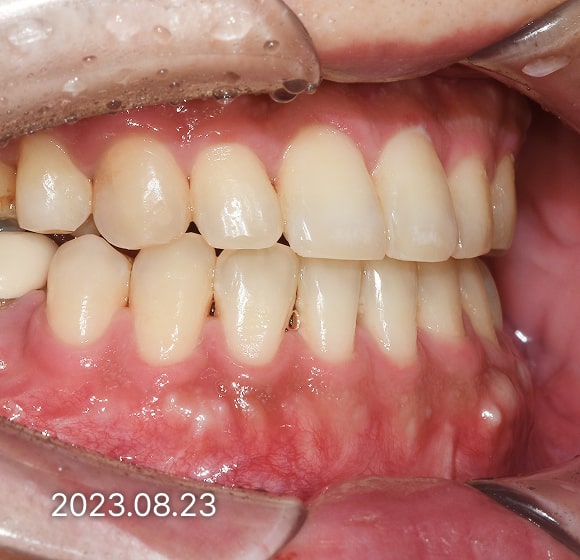

BEFORE / AFTER

전후 변화로 보는 치료사례

본 사진은 진심을담은치과교정과 치과의원에서

치료한 환자의 동일 인물 전·후 사진입니다.

개인의 구강 상태 및 관리 방법에 따라 통증 및 잇몸 염증,

턱관절 불편감 등의 부작용이 발생할 수 있습니다.

치료 전 치료 후

덧니, 삐뚤한 치열

돌출입

반대교합(비수술)

성장기 교정

과개교합

개방교합

치열공간, 벌어진 앞니

매복치아

악교정 수술 교정

결손치

부분교정

인비절라인